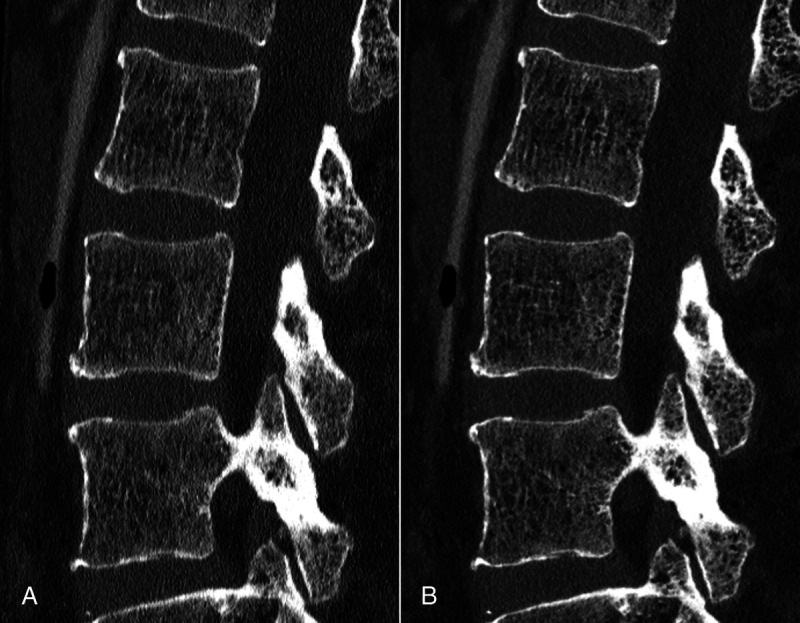

摘要:光子计数探测器(PCD)是近年来医学成像领域最具影响力的技术发展之一。PCD-CT 扫描仪在许多方面都超越了采用能量集成探测器技术的传统系统,可为所有放射亚专科提供卓越的空间分辨率和剂量效率。肌肉骨骼(MSK)成像需要在同一次扫描中详细显示骨小梁微结构和广泛的解剖学覆盖范围,因此 PCD-CT 的卓越性能尤其使其受益匪浅。然而,由于 PCD-CT 为用户提供了大量图像采集和重建的定制选项,因此 MSK 放射科医生需要熟悉该扫描仪,才能充分挖掘其潜力。从基于滤波器的光谱整形以减少全视野超高分辨率扫描的伪影,到单源或双源多能数据的后处理,几乎所有成像任务都可以通过 PCD-CT 的优化方法来完成。本综述旨在概述迄今为止 PCD-CT 在 MSK 成像中最有前景的应用,说明目前的局限性,并强调未来研究和发展的方向。

Abstract: Photon-counting detectors (PCDs) have emerged as one of the most influential technical developments for medical imaging in recent memory. Surpassing conventional systems with energy-integrating detector technology in many aspects, PCD-CT scanners provide superior spatial resolution and dose efficiency for all radiological subspecialities. Demanding detailed display of trabecular microarchitecture and extensive anatomical coverage frequently within the same scan, musculoskeletal (MSK) imaging in particular can be a beneficiary of PCD-CT's remarkable performance. Since PCD-CT provides users with a plethora of customization options for both image acquisition and reconstruction, however, MSK radiologists need to be familiar with the scanner to unlock its full potential. From filter-based spectral shaping for artifact reduction over full field-of-view ultra-high-resolution scans to postprocessing of single- or dual-source multienergy data, almost every imaging task can be met with an optimized approach in PCD-CT. The objectives of this review were to give an overview of the most promising applications of PCD-CT in MSK imaging to date, to state current limitations, and to highlight directions for future research and developments.